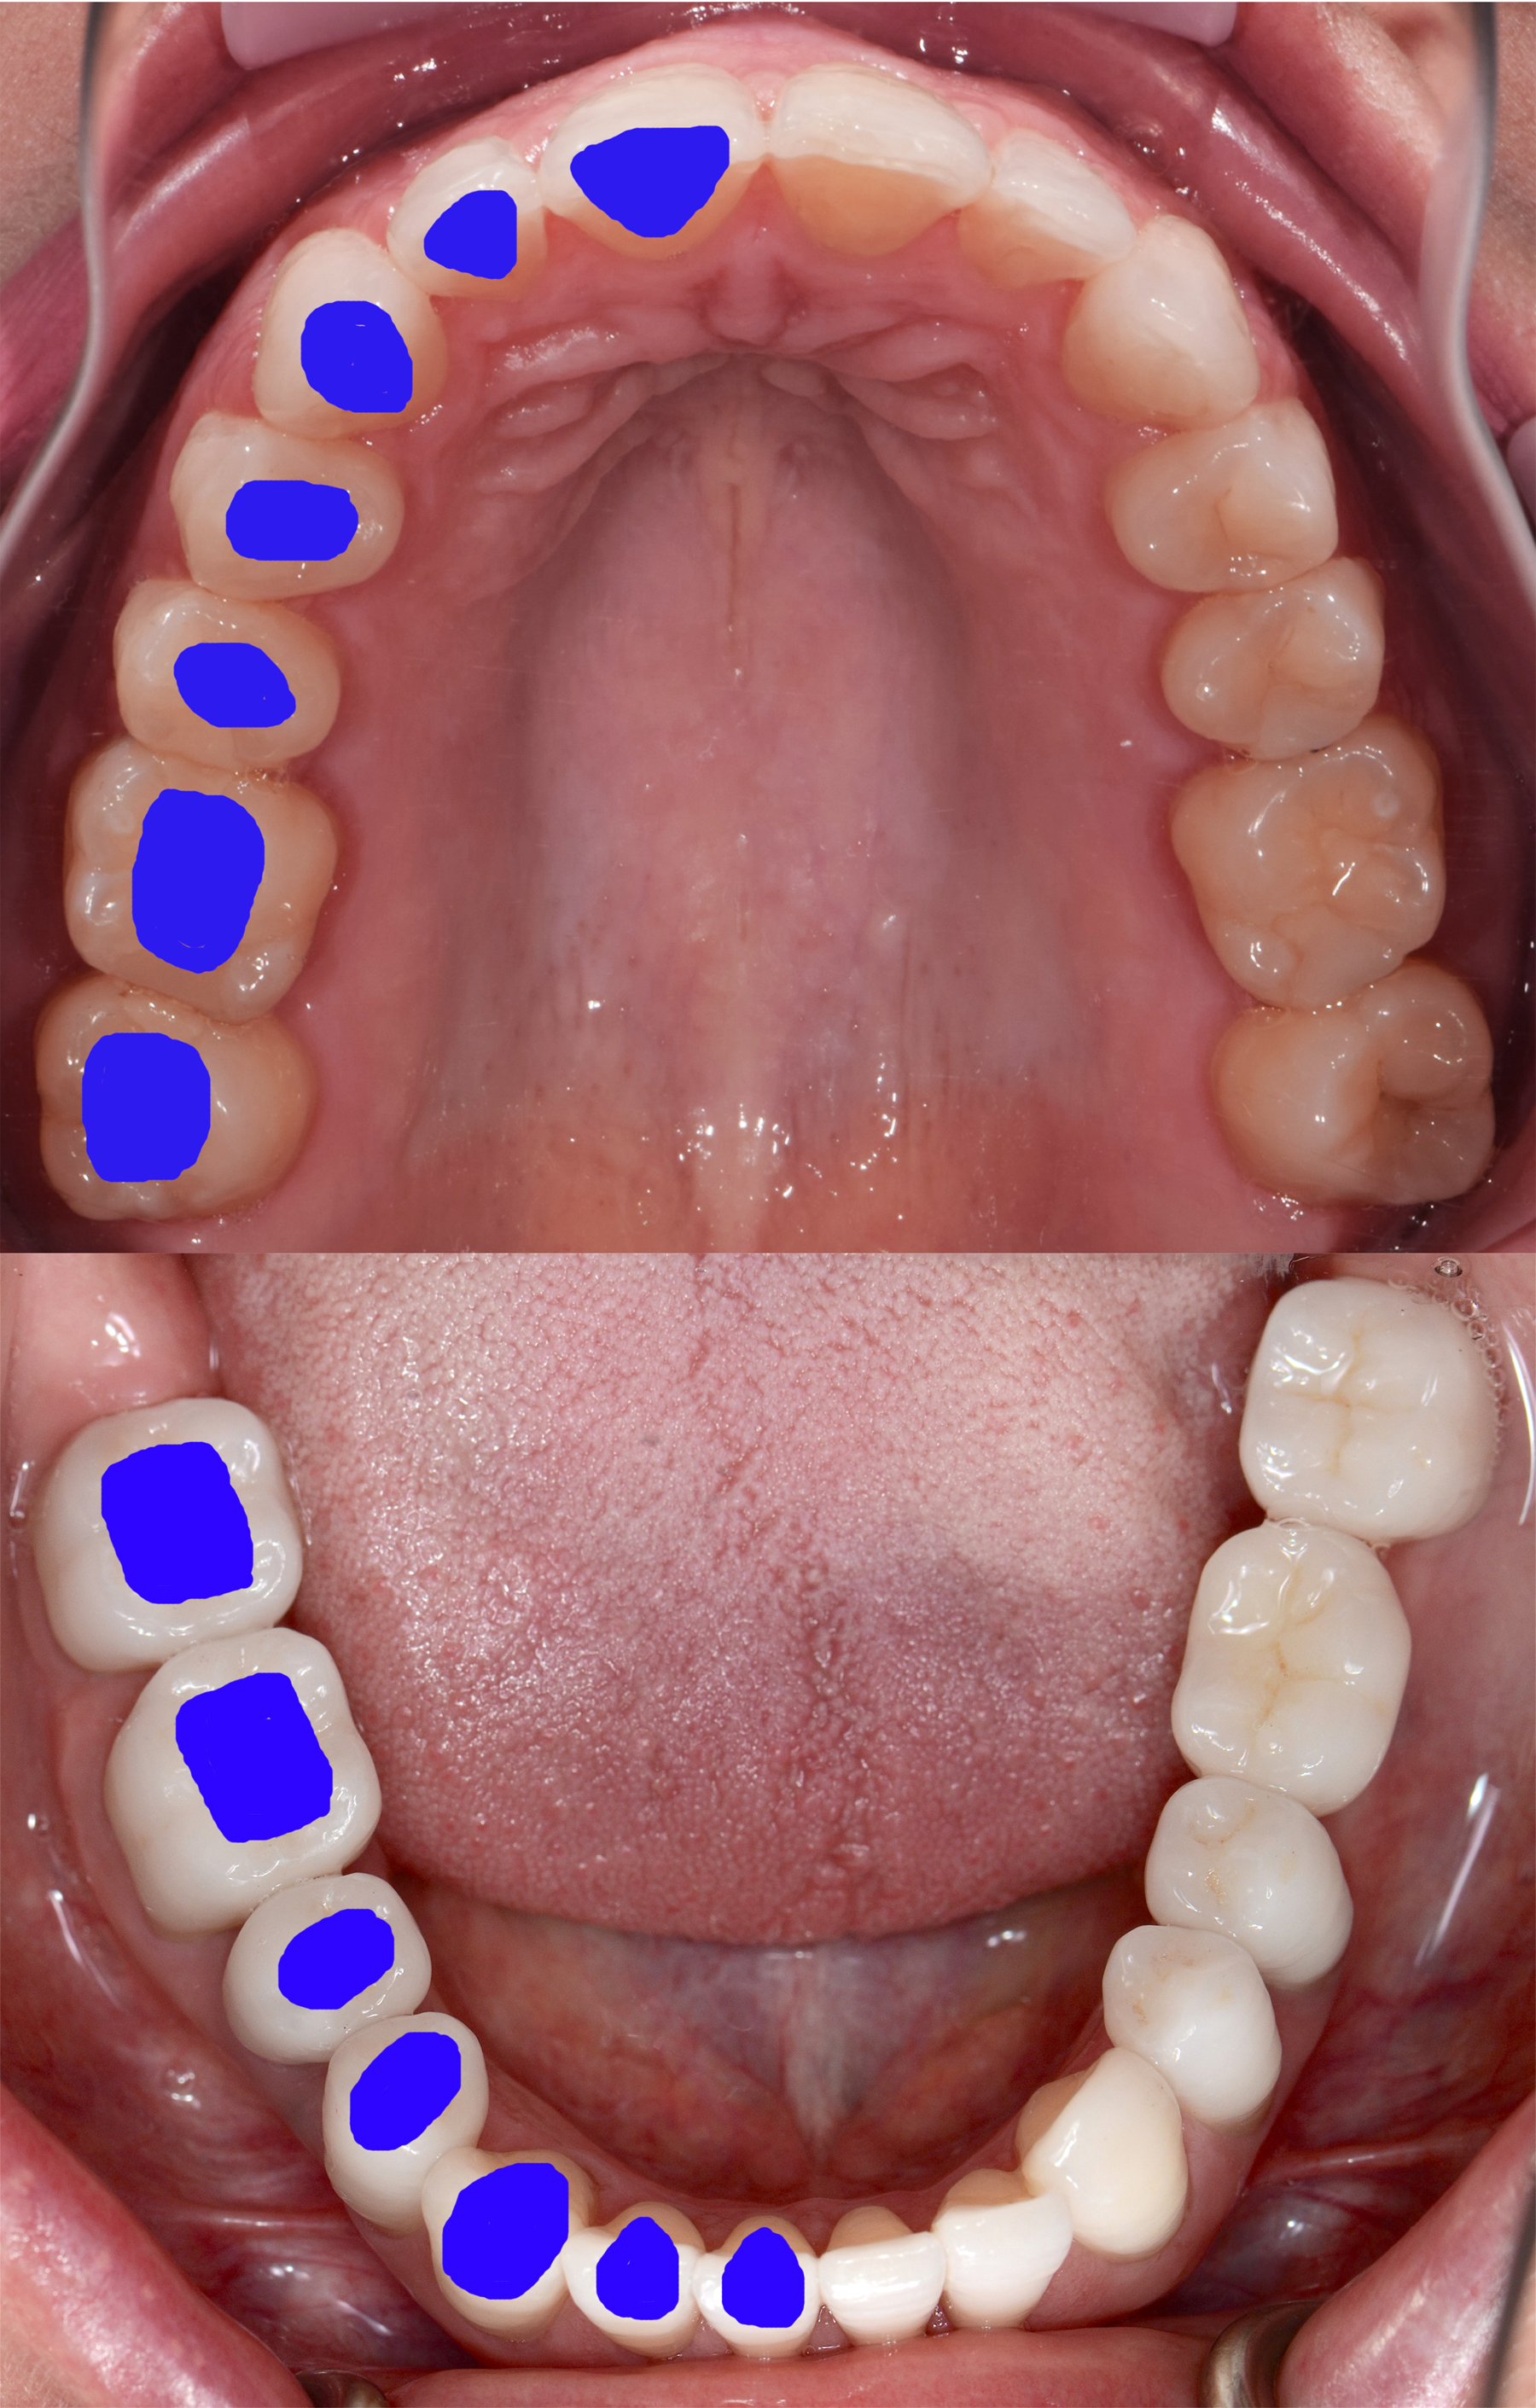

It can be challenging to replicate not only the crown portion of the tooth but also the entire tooth anatomy. The cross-section of teeth at the gingival margin have various shapes, such as triangular, rhomboidal, and ovoid, depending on the type of tooth it is (Figure 1). The challenge arises because implants are round in cross-section at the platform and the clinician needs to transition to the specific shape of the natural tooth to provide natural-looking esthetics that mimic the profile of the tooth. Selecting the optimal implant diameter for the space available is dependent on not only the mesial-distal dimension but also the buccal-lingual dimension.20,21 Use of an implant with a narrower diameter than the mesial-distal space available may complicate emergence profile and lead to proximal food traps and adversely affect esthetics (Figure 2). This has clinical relevance in both the anterior and posterior areas of the mouth.

Fig 1. The cross-sections of various teeth, as identified by the blue markings, demonstrate the different shapes of soft-tissue profile needed at the implant platform to replicate a natural tooth emergence profile.

Figure 1